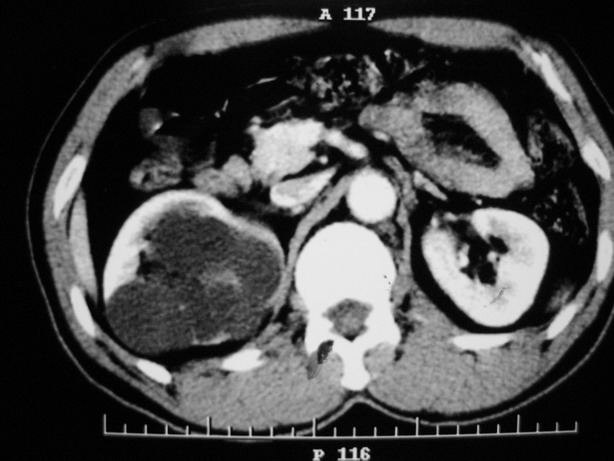

标题: CT10772:男性,48,右肾盂旁多囊性占位! [打印本页]

标题: CT10772:男性,48,右肾盂旁多囊性占位!

男性,48,体检发现,平时无症状。

收集期:

延迟期造影剂没有进入囊性病灶内考虑多发性肾囊肿,包括一个盂旁囊肿。

肾盂旁多囊性占位,有实性成分,增强有轻度强化,收集期病变内无造影剂显影。诊断肾盂旁囊肿,有实性成分无法解释,查书后诊断为:多房性囊性肾瘤!!不知大家同意否?????????对本病知道不多,望大家不吝赐教!!